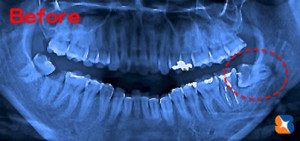

抜歯前のレントゲン

コラム「抜歯前のレントゲン」の画像